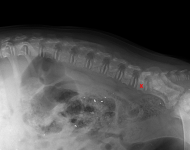

MVDr. Meloun: Lumbosakrální přechodový obratel